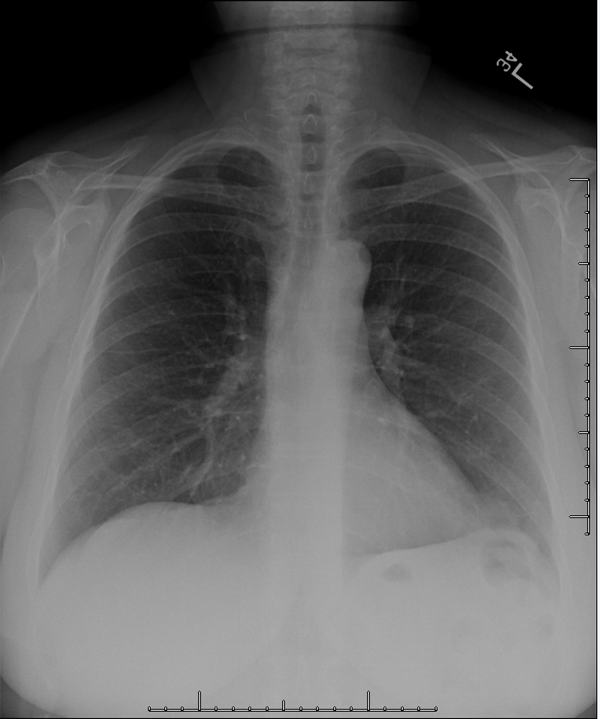

PBL 1311 Normal Chest X-ray

Chest X-ray 1, PA